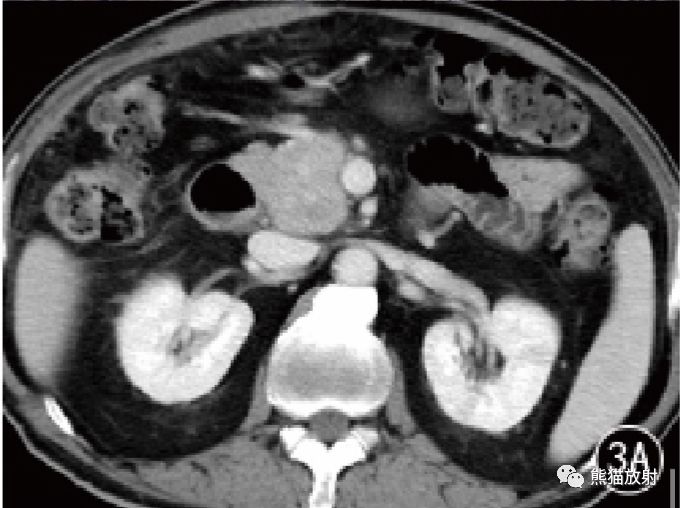

图3 男,63 岁,AIP 胰腺体尾部弥漫性病变并胰头部局灶性病变。CT门静脉期显示胰头部均匀强化病灶和体尾部肿胀呈腊肠样。